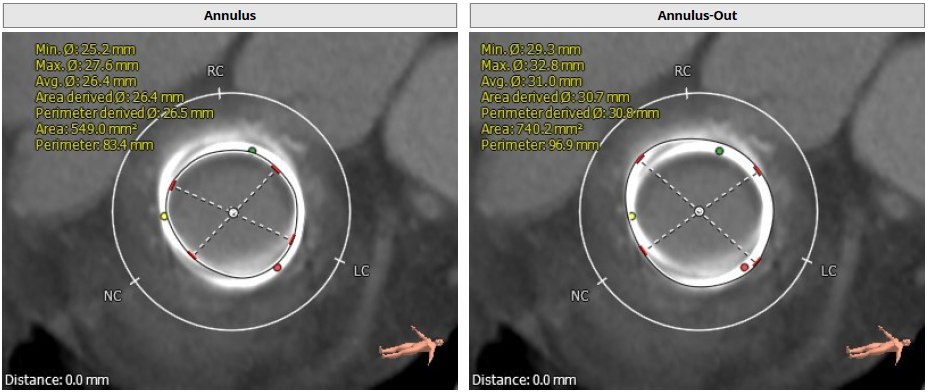

1. 二尖瓣生物瓣换瓣术后:原生物瓣金属环周长折算内径26.5mm,外径30.5mm(金属环存在重建错位),瓣架高度20.6mm;

生物瓣金属环周长折算内径26.5mm,外径30.5mm